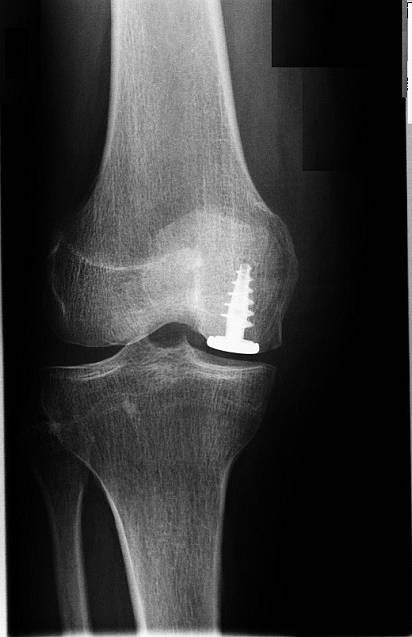

Eine isolierte Arthrose hinter der Kniescheibe kann durch ein speziell angepasstes Implantat behandelt werden. Das Hemicap-Implantat formt die retropatellare Gleitrinne auf dem Oberschenkelknochen (Trochlea) nach. © Prof. Dr. med. Ostermeier

Wenn die retropatellare Arthrose beide Gelenkflächen – Patella und Oberschenkel – betrifft, kommt eine retropatellare Prothese mit patellaseitiger PET-Gleitschicht zum Einsatz. Dieses Röntgenbild zeigt nur die Metallkomponente. Der Kunststoff wird im Röntgen nicht dargestellt. © Prof. Dr. med. Ostermeier

Wenn die Knorpelschicht hinter der Kniescheibe noch intakt ist, kann die Versorgung durch ein patellofemorales Hemicap-Implantat als Oberflächenersatzprothese erfolgen. Dieses Implantat deckt das patellofemorale Gleitlager (Trochlea) ab und berührt die patellaseitige Knorpelschicht.

Wenn die patellaseitige Knorpelschicht ebenfalls schon abgenutzt ist, muss die Prothese mit einem Kunststoff-Gleitpartner implantiert werden. Bei der patellofemoralen Prothese verbindet sich das Implantat im Femur (Oberschenkelknochen) mit einer Polyethylen-Gleitschicht, die an der Patella (Kniescheibe) implantiert ist.

Beide Versorgungstypen dienen der raschen Sanierung und Eindämmung der retropatellaren Arthrose. Die Arthrose kann dann nicht mehr entzündlich aktiviert werden und den Rest des Knies in Mitleidenschaft ziehen. Die typischen Symptome wie Schwellung, Anlaufschmerzen oder Belastungsschmerzen hinter der Kniescheibe behandelt das retropatellare Implantat zuverlässig.